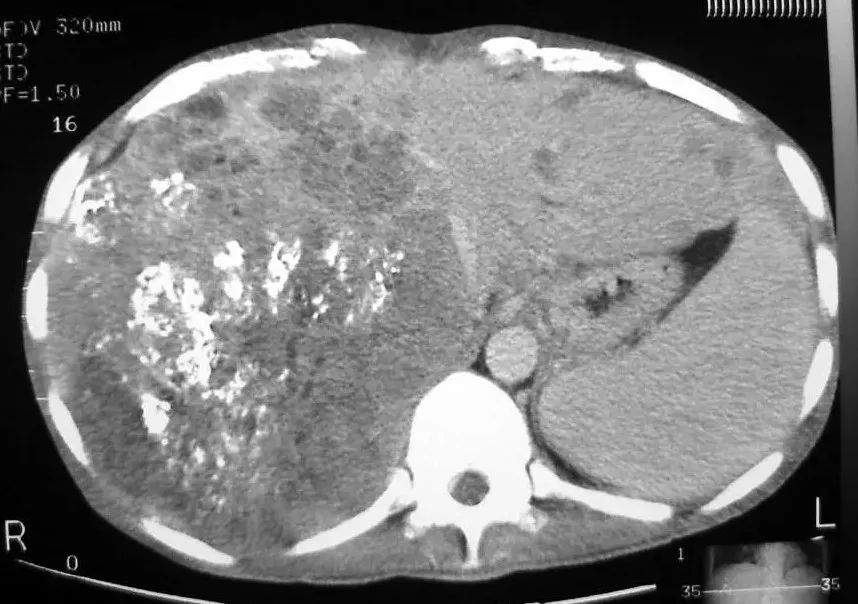

巨块型肝癌,很难通过一次性介入治愈

对于大多数的恶性肿瘤来说,由于其早期没有症状,在发现时往往已经是不能手术的中晚期,一次性的介入治疗是很难达到治愈目的的。因此,多次介入治疗常常是必要的。

还是以介入治疗失去手术切除机会的恶性肿瘤来说:由于肿瘤较大,出于保护患者的目的,一次介入所投入的抗癌药、栓塞剂等必须有所节制,否则就会造成“肿瘤死了,人也死了”,那是不能让人接受的。所以介入后,难免会有一些肿瘤细胞得以残存。而这些残存的肿瘤细胞可不是“吃素的”,它们又会疯狂地“生儿育女、发展壮大”!

首先,应该注意治疗力度。这如同“拔河”一般,在可耐受的情况下,应该尽力杀灭更多的肿瘤细胞。因为,如果肿瘤生长的速度如果大于介入杀灭的速度,肿瘤就会继续发展,患者难免死亡;而如果介入杀灭的速度大于肿瘤的生长速度,肿瘤则就会缩小甚至最终得到治愈。